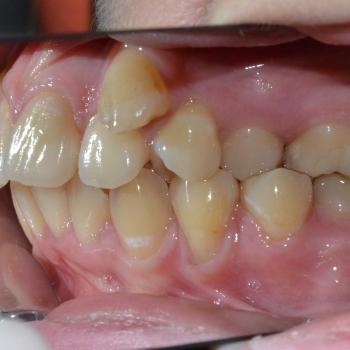

Luca saját elhatározásból, az alsó és felső fogív torlódása, de főleg a két felső szemfog ectopiás helyzete miatt keresett fel. Már elsőre pillantásra látható volt és Luca is sejtette, hogy foghúzások nélkül az Ő esete nem oldható meg,de szerencsére ez nem tántorította el a céljától.

Közös döntés eredményeként fém önligírozó fogszabályozót választottunk, illetve a felső kisőrlők, illetve egy darab alsó metszőfog eltávolítására került sor. Az alsó metszőfog eltávolítása elsőre szokatlannak tűnhet, de a fogszabályozásban ez bevett gyakorlat hiszen esztétikai problémát nem okoz és a húzás által biztosított plusz hely rögtön a megfelelő helyen áll a rendelkezésünkre.